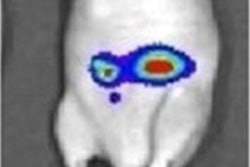

Mo-99 is the parent isotope of technetium-99m (Tc-99m), a widely used radioisotope in medical diagnostic imaging, while I-131 is used for imaging and to treat hyperthyroidism. Xe-133 is inhaled for lung imaging, and Sr-89 is used to help relieve bone pain that can occur with certain types of bone cancer.